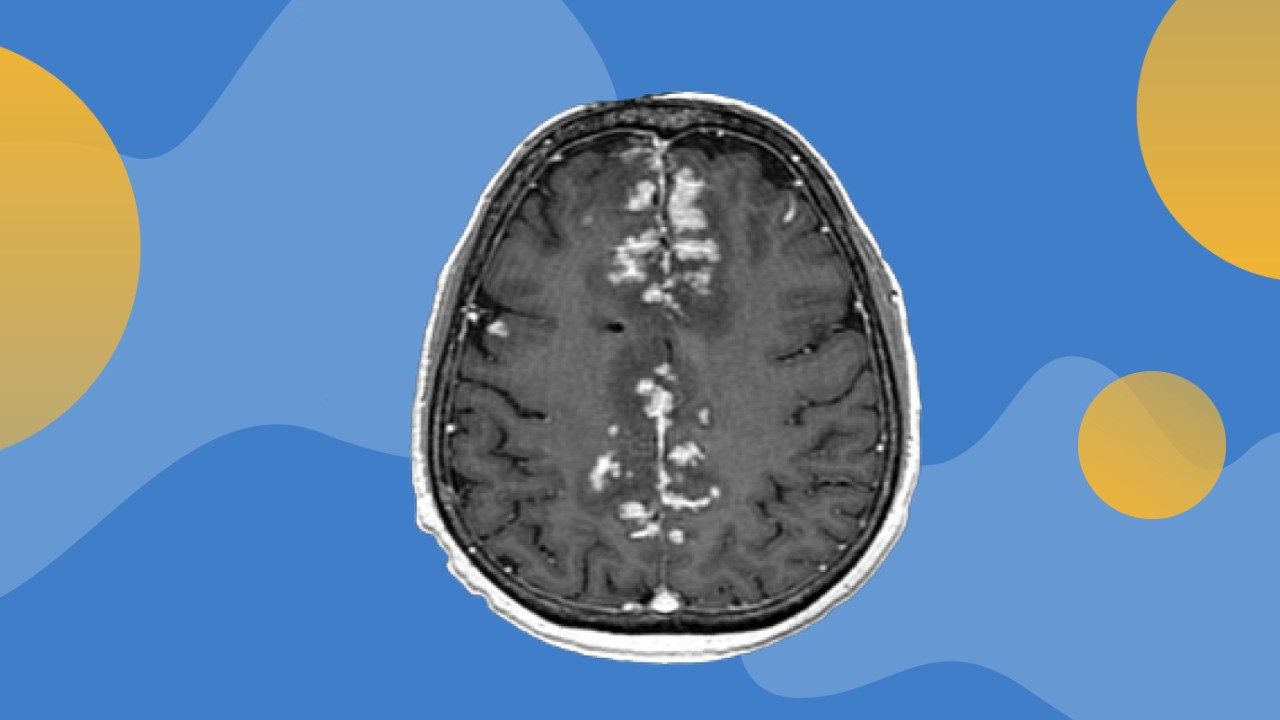

Combined delivery of engineered virus with immunotherapy is safe and improves outcomes in subset of patients with glioblastoma

Intratumoral delivery of an engineered oncolytic virus (DNX-2401) targeting glioblastoma (GBM) cells combined with subsequent immunotherapy...

mRNA delivered by extracellular vesicles induces immunotherapy response in glioblastoma

A team of researchers at The University of Texas MD Anderson Cancer Center has developed a new method for using extracellular vesicles to...